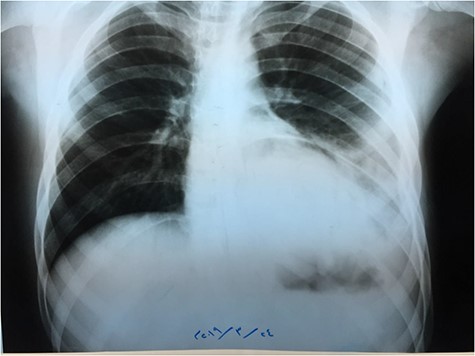

Chest X-ray (Fig. 1) showed an increased density in the left lower zone of the lung. Forty-eight hours later, the patient arrived at the ER along with the computed tomography (CT) scan (Fig. 2). He was in a very poor general condition with pallor, severe dyspnea and clouding of consciousness. Physical examination showed the absence of the left lung sounds, shifted apex beat of the heart to the right and a thready pulse and a blood pressure of about 80/40 mmHg.